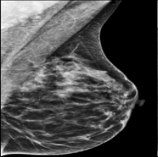

The 136 true outliers are classified into seven categories by the professional radiologist: implant, pacemaker, cardiac loop recorder, improper radiography, atypical lesion/calcification, incorrect exposure parameter and improper placement. It is worth noting that, despite the fact that mammograms with implants were eliminated during the preprocessing step (see Section 2.6), there were still mammograms with implants remaining since they were incorrectly categorised as having no implants. Figure 1 depicts representative outliers for each category, and Table. 4 displays the number and percentage of outliers in each category given that that the total number of true outliers is 136.

Figure 1: Examples of true outlier subgroups in the ADMANI dataset. From left to right and top to bottom, the outlier types are: implant, pacemaker, cardiac loop recorder, improper radiography, improper radiography, atypical lesions/calcification, incorrect exposure parameter, improper placement. Improper radiography is classified into two subtypes: those with heterogeneous pectoral muscle and the rest, respectively.